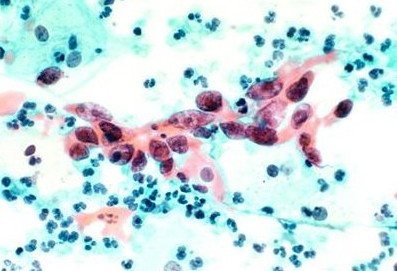

Полиморфная палочка в мазке у женщины определяется с помощью бактериологического анализа. Для проведения диагностики сдают мазок на микрофлору. С помощью мазка трудно определить конкретный вид бактерий, которые преобладают в микрофлоре.

Для этого и проводится бактериологический посев, на основе которого не только определяют вид поселившейся бактерии, но и определяют чувствительность её к антибиотикам. Полученные результаты дают возможность врачу диагностировать гинекологические заболевания: кольпит, вагиноз. Часто большое скопление полиморфных палочек указывает на развитие вагинального дисбактериоза.

Нередко людей смущает запись в анализах о наличии в мазке полиморфных палочек. Это подразумевает, что во взятом для исследования материале находятся различные виды палочек.

Понятие полиморфные палочки – это общее название множества видов микробов, которое объединяет микроорганизмы, отличающиеся по размеру и имеющих форму палочек.

Представители полиморфно палочковой флоры могут оседать на стенках влагалища в виде белого налета, который обнаруживает гинеколог при осмотре. Точно определить, что это за бацилла трудно, поэтому, как правило, назначается бактериоскопия. Исследуемый материал после забора помещается в специальную среду, где микробы прорастают.